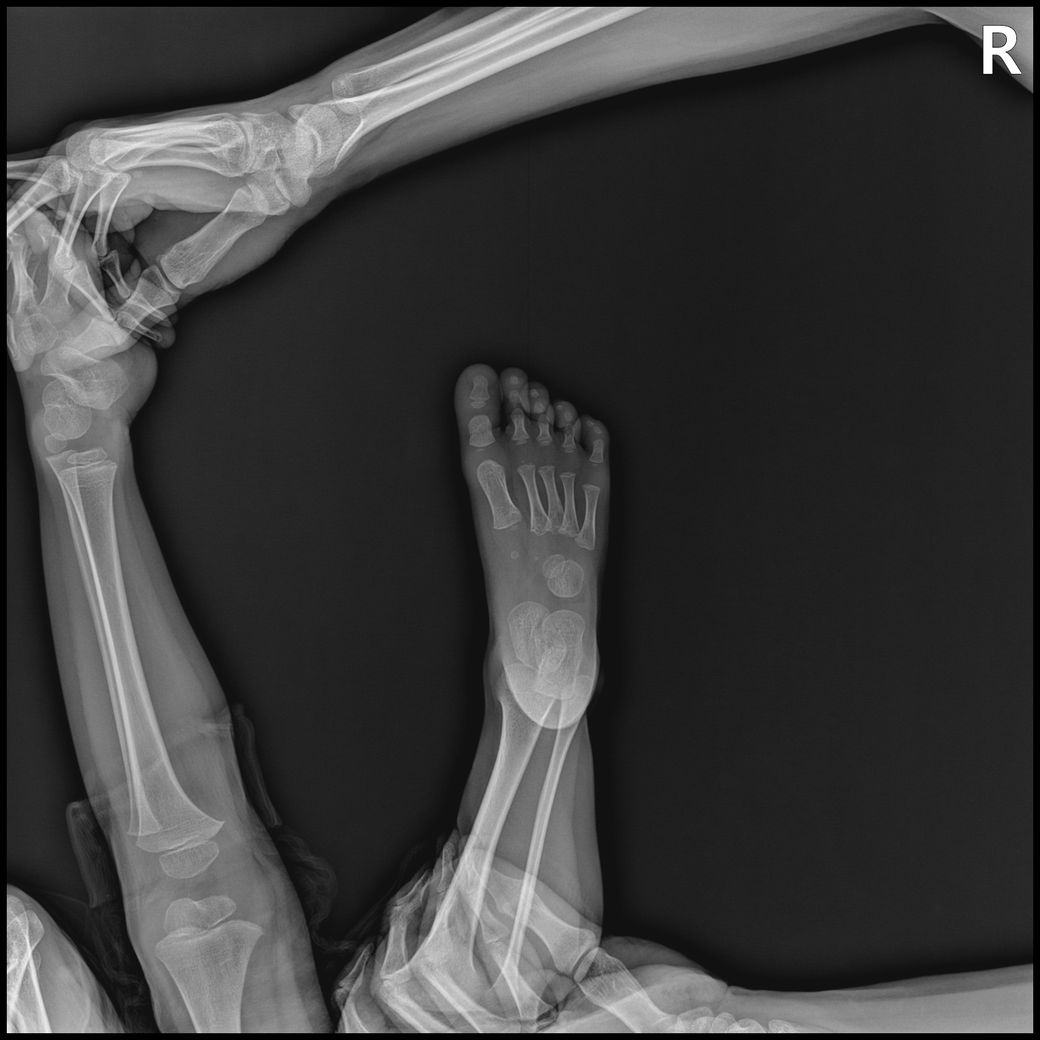

아기 손발 엑스레이를 찍게되었는데요.

손목, 발목까지 6-8장 찍기로 안내받았으나,

고관절,복부일부,생식기등 민감부위등이 추가로 촬영되었고

발도 다리가 다 찍혔고 총 19장이 찍혔습니다.

- 몸통일부+손같이찍힘 : 6장

- 손부터 팔꿈치까지 : 3장

- 발~다리사진 : 10장